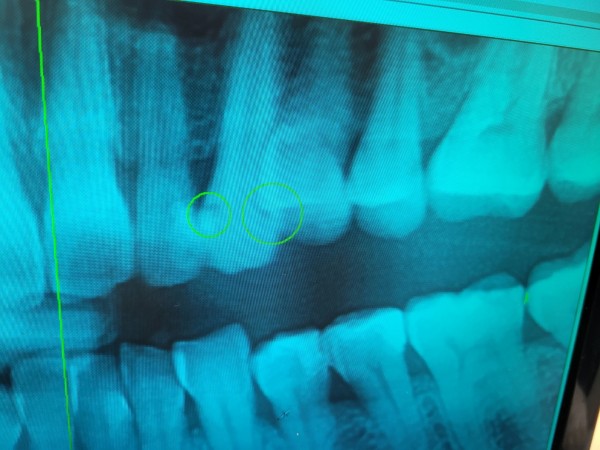

타 병원에서 엑스레이상에 체크된 아래 어금니 세개와

윗 이 한개 치료가 필요하다고 들었는데요..

아래 어금니 세개와 윗 이 한개 이렇게 4개 치아 모두 치료를 받아야 하는 상황인건지 궁금하구요.

치료를 할 경우 아래쪽 끝에서 두번째 어금니는 엑스레이상으로 봤을때 신경치료가 꼭 필요한 상황인지 궁금합니다.